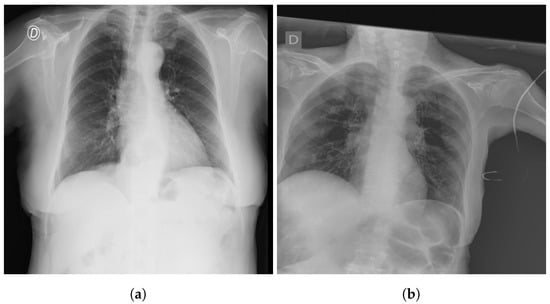

The SIIM-FISABIO-RSNA COVID-19 [32] is a public dataset provided by Society for Imaging Informatics in Medicine (SIIM). Each CXR image comes with labeling to identify and localize COVID-19 abnormalities in chest radiographs. The competition is an object detection and classification problem. In our study, we used all images annotated COVID-19 for the classification. The train dataset comprises 6334 CXR images in DICOM format, which were de-identified to protect patient privacy. All images were labeled by a panel of experienced radiologists for the presence of opacities, as well as overall appearance. The test set contains 1264 CXR images. Figure 2 shows an examples of CXR from the SIIM-FISABIO-RSNA COVID-19 dataset.

Figure 2.

Example of SIIM-FISABIO-RSNA COVID-19 images: (a,b) [32].